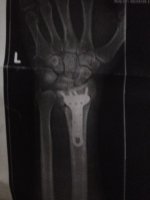

I spent some time on it to make it rideable and despite the lack of compression it still went like a shower of sh*t. Wheelstanded in every gear. (im 50kg/125lb) ive ridden 2strokes all my life and am seriously addicted to them, but for some reason this bike has some serious sting to it. I ended up coming a gutser and shattered my wrist so im inthe process of rebuilding the top end.